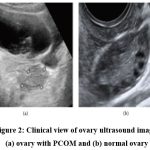

After completing image collection, the process for obtaining clinical data was begun to investigate how clinical data affected the diagnosis of PCOS. This procedure seeks to obtain clinical data for patients whose ultrasound images were gathered in the previous phase from the hospital system. The features were chosen with the assistance of professional judgments and with consideration of previous studies that identified the significance of those attributes on PCOS diagnosis in some manner.11,22 There are many clinical data points that are lacking and need further validation, as we discovered while collecting clinical data for 391 patients whose ultrasound photos were already accessible. Ultimately, a dataset has 285 samples and 22 characteristics. The clinical dataset is composed of 156 non-PCOS individuals and 129 PCOS cases. Diagnoses for patients in the dataset are made using laboratory results, medical records, and radiologist analysis of ultrasound pictures to distinguish between PCOS and non-PCOS. Characteristics are divided into four categories, including demographics, vital signs, lab results, and doctors’ comments, such as cycle regularity. The dataset has two data types, four nominal/categorical features, and 17 numeric features. Additionally, only photos that clearly show the ovary were chosen for the investigation. Radiologists divided the selected images into two categories for categorization: the sonographically visible PCOM and those with a normal morphology (non-PCOM). As seen in Figure 2, PCOM is represented by an ovary with several, uniformly sized, peripherally positioned follicles that are smaller than one centimetre. The dataset of photographs consists of 391 images which has clinical record result of 127 PCOM, and 264 normal ovaries that are not PCOM.

Four categories can be used to group the characteristics, including demographics, vital signs, laboratory tests, and medical notes. The dataset has two data types, four nominal/categorical features, and 17 numeric features. Additionally, only photos that clearly show the ovary were chosen for the investigation. Radiologists divided the selected images into two categories for categorization: those with a non-PCOM and those displaying the sonographic PCOM. Figure 2 illustrates an ovary with numerous, uniformly sized follicles that are positioned peripherally and have a diameter of less than 1 cm. This is the definition of the polycystic ovarian morphology. 391 pictures, 127 PCOM, and 264 normal ovaries that are not PCOM make up the image dataset.